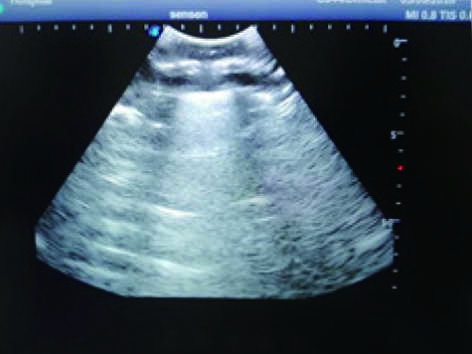

2)  Real clinical ultrasound images with clear muscles, connective tissues, lungs and pleural structures